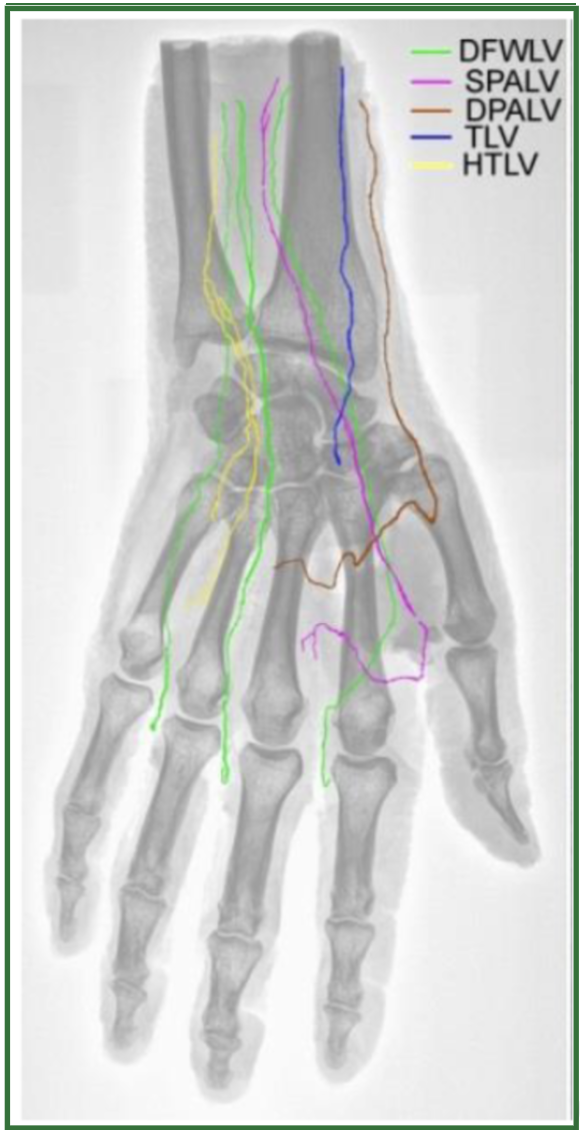

Research advanced significantly in 2005 with the development of a novel approach to lymphatic evaluation. It was not until 2018, however, that detailed mappings of the deep lymphatic structures in the hands emerged. Scientists identified and illustrated five distinct groups of deep lymphatic vessels within the hand. Each group starts in the palm and initially follows varied pathways. They then converge in the regions between the fingers, transitioning from the underside of the hand to the dorsal surface, ultimately directing flow toward the wrist and into adjacent lymph nodes.